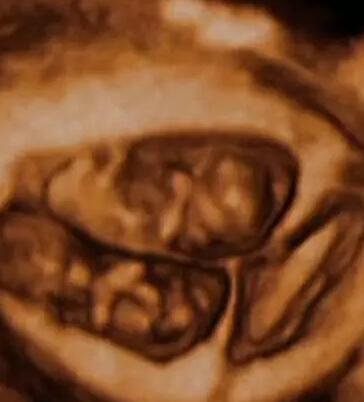

双胞胎在上演“子宫中接吻”。多胞胎被认为因子宫中的互动而受益,这些互动有助于他们更快地发育。

这对双胞胎在进行头顶头的肉搏战。

有时候,这些推挤看起来像是升为了相互击打。